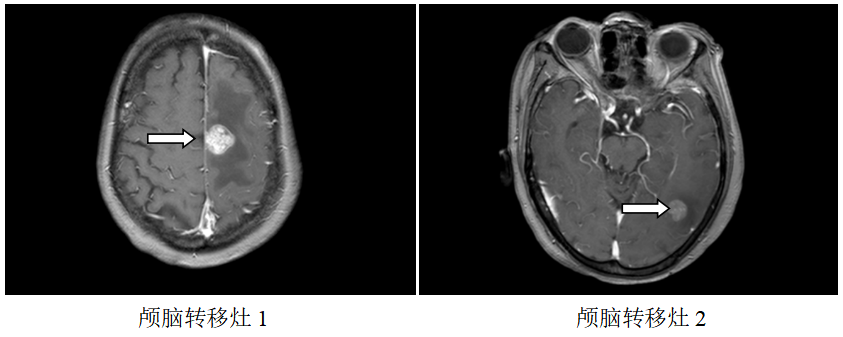

颅脑MR:左侧额、枕叶脑转移瘤;

图1.2019.7.5影像(基线评估)

诊断:食管胃交界腺癌腹腔、腹膜后、左腋窝、左锁骨区淋巴结转移脑转移(cT4aN3M1,IV期,HER2扩增,MSS,PD-L1-)

局部放疗:2019.7.23~2019.8.7予脑转移灶调强放疗DT3900CGy/13F。

再次放疗:2020.06.04复查颅脑MR:原左侧额、枕叶脑转移瘤较前缩小,右侧颞叶新增转移瘤,于2020.6.15-6.26予脑转移灶调强放疗DT3000CGy/10F。